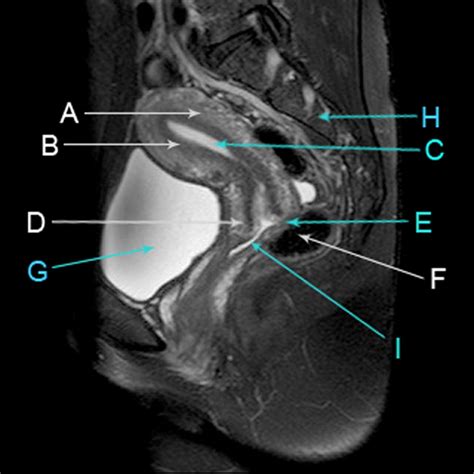

The primary goal of an MRI Pelvis Without Contrast is to provide a clear view of the soft tissues, bones, and reproductive or urinary organs located between the hips. Because MRI provides superior soft-tissue contrast compared to CT scans or X-rays, it is the gold standard for identifying abnormalities that might not be visible through other modalities.

• mri pelvis female

• mri pelvis female with contrast

• pelvic mri with contrast images